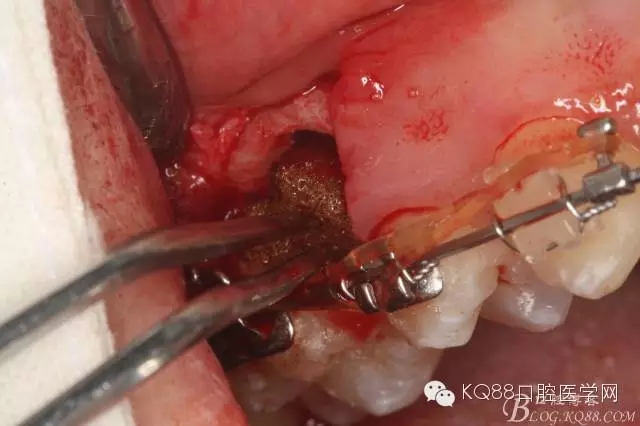

圖15 .微創(chuàng)挺把15牙根縱分成近遠中兩塊

圖16.微創(chuàng)挺挺松近中根面部分,從16與14之間間隙出來

圖17.血管鉗取出近中部分15牙根

圖18.取出近中部分后,接著挺松15牙根的遠中部分